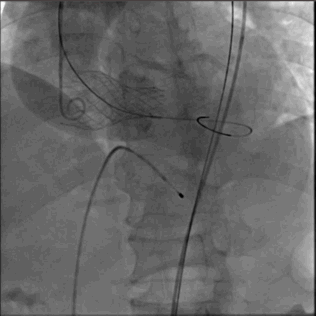

5.完全释放瓣膜

6.猪尾导管拉回 放置新的人工瓣膜工作区域上方造影

7.瓣膜支架未完全打开,返流 PVL均存在,决定后扩

8.支架展开形态良好 返流大幅度减少

9.仅在钙化严重,窦交界区域有PVL,符合术前预估